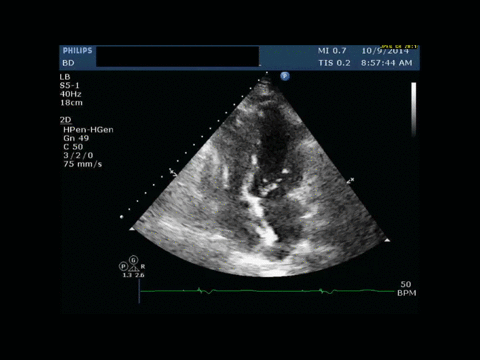

History of Present Illness: A 73-year-old female presents to the emergency room with a 3-day-history of chest pain and hallucinations. She is initially treated for urinary tract sepsis, however eight hours after presentation, she suddenly became unresponsive and hypotensive, requiring intubation and initiation of vasopressors. Initial focused-bedside ultrasound aiming to evaluate etiologies of shock reveals septal wall hypokinesia.

With worsening hypotension, serial bedside ultrasound was performed.